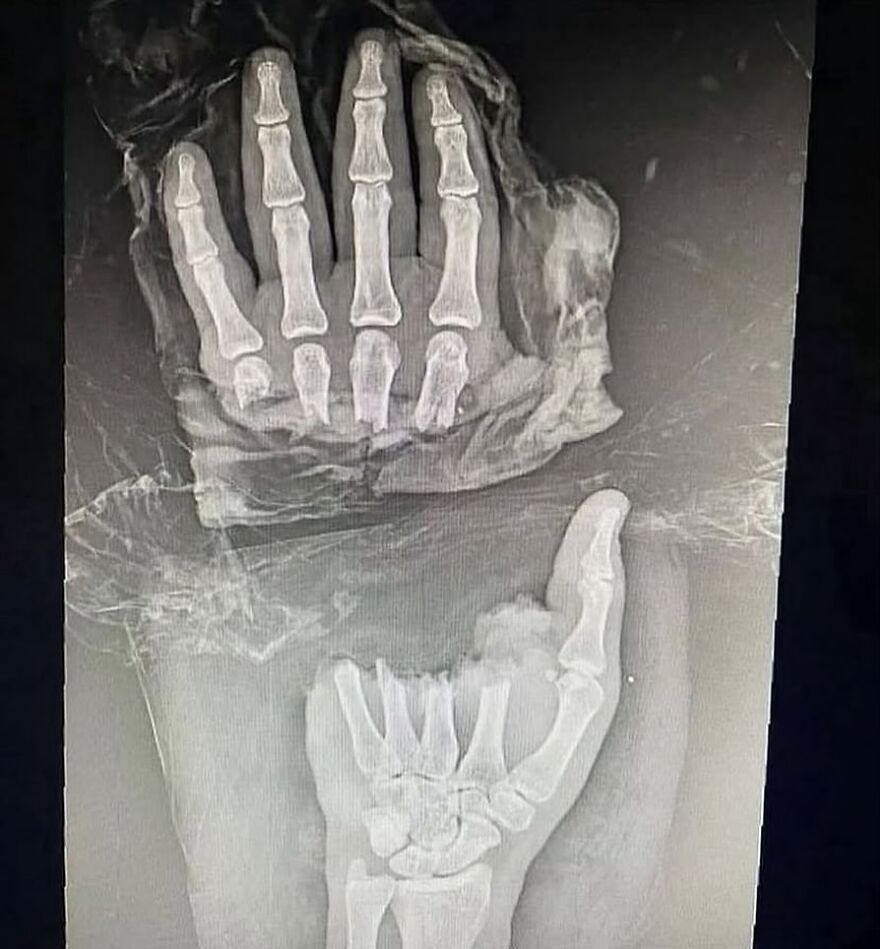

Raynaudov syndróm